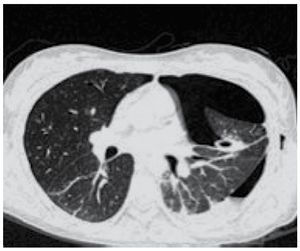

Durante el seguimiento, se solicitó TAC de tórax por presentar hidroneumotórax izquierdo espontáneo, así como neumotórax derecho, además se evidenció parénquima pulmonar bilateral con imágenes quísticas (Figuras 3 y 4).

Figura 3. Neumotórax espontáneo izquierdo y mínimo derecho. Nótese las áreas quísticas visibles en parénquima derecho.

Figura 4. Neumotórax espontáneo izquierdo, con quistes en parénquima pulmonar.